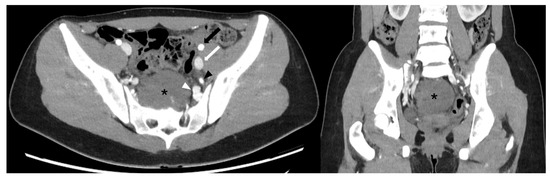

An Angio-CT scan was performed preoperatively (Figure 2) and used for 3D reconstruction of the vascular structures and their relationship with the lesion, utilizing Brainlab® (BrainLAB AG, Germany) planning software (Figure 3). Additionally, a 3D digital reconstruction of the pelvic mass, with a total volume of 240 cm3, was created from the contrast-enhanced MRI and fused with the Angio-CT data, allowing for precise 3D planning of the tumor’s position relative to surrounding vascular structures.

Figure 2. Angio-CT scan, axial (left) and coronal (right) views. The presacral mass (black asterisk) is in close contact with vascular structures, including the internal iliac vein (white arrowhead) and internal iliac artery (black arrowhead). In contrast, the external iliac artery (black arrow) and vein (white arrow) are spared.